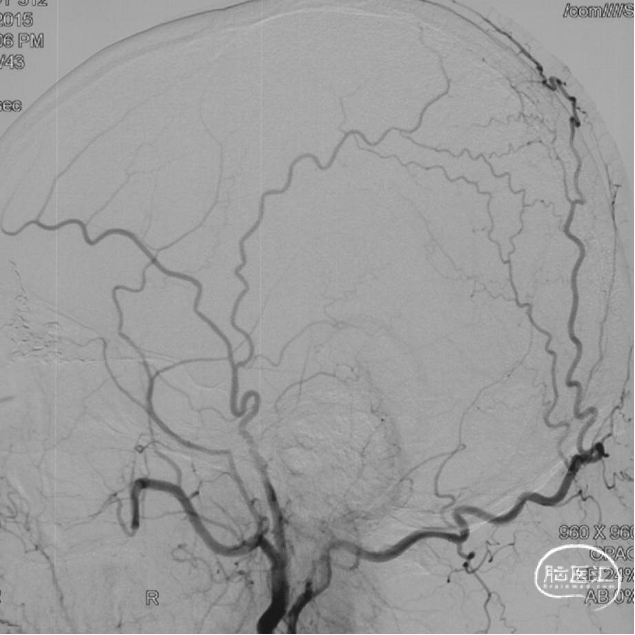

最终造影瘘口完全不显影。

双侧脉络膜染色正常。

术后三个月造影复查,双侧颈内动脉、颈外动脉造影均未见静脉早显,DAVF治愈。